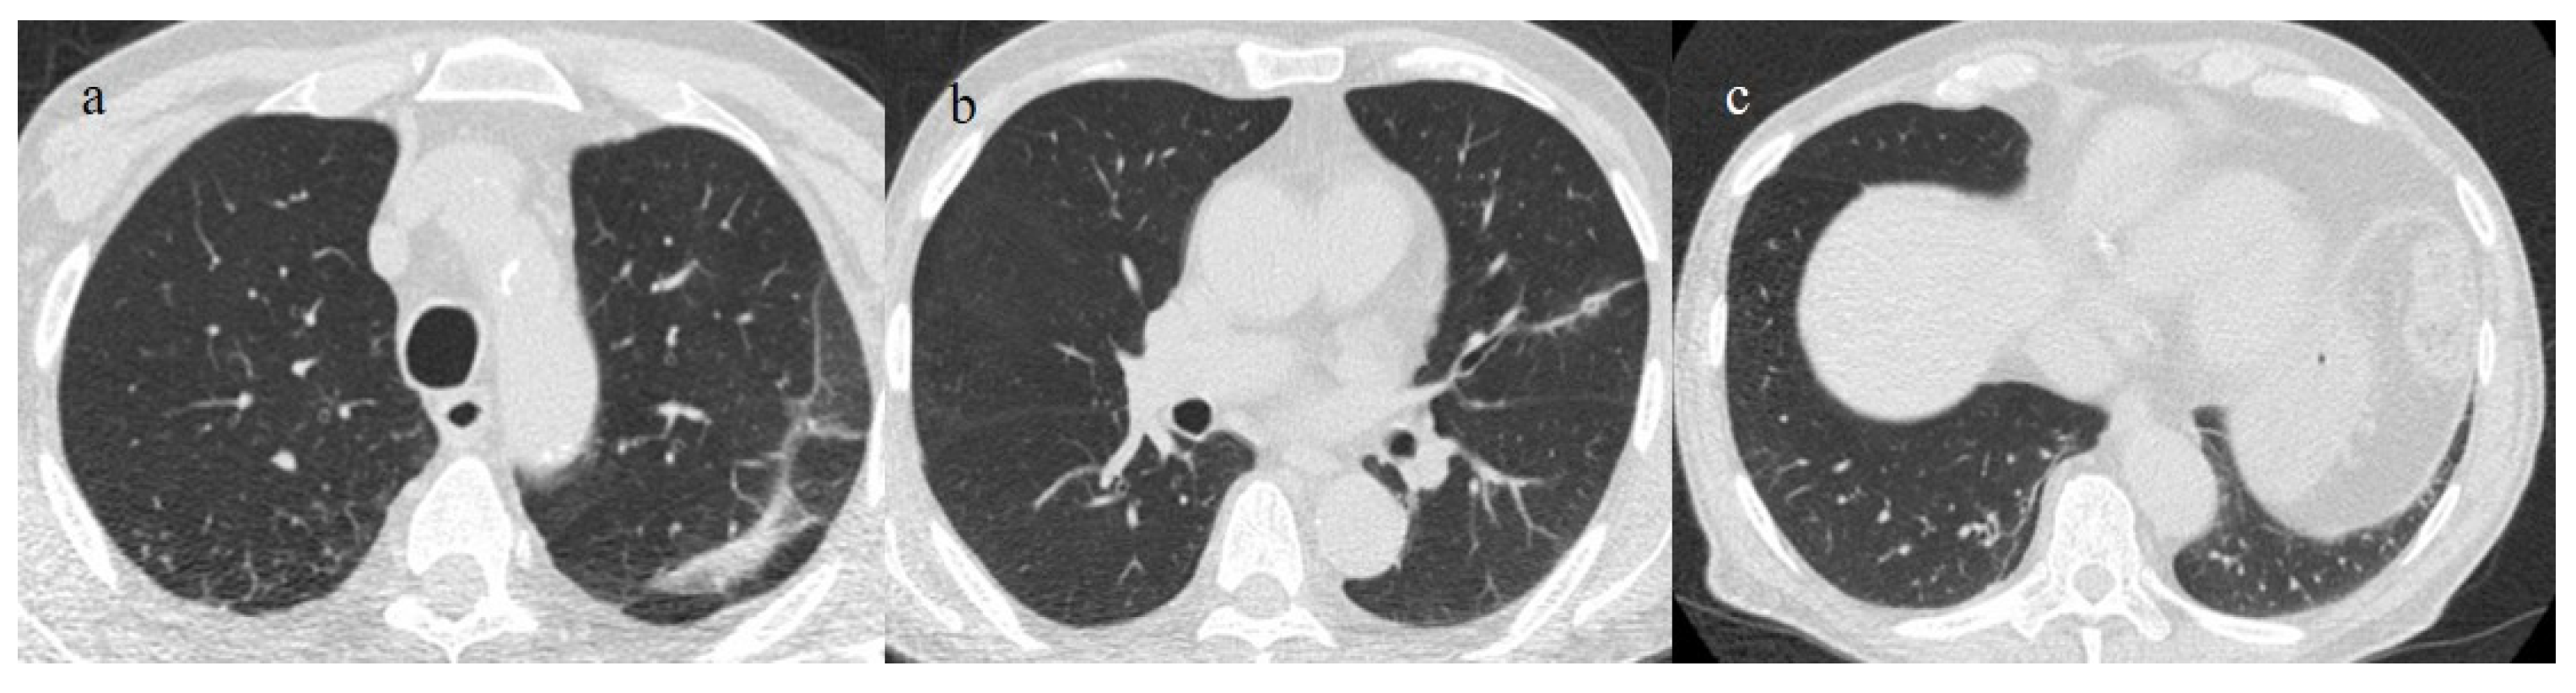

| Typical Appearance | GGOs with a crazy-paving pattern and consolidations in a peripheral and posterior or central-peripheral distribution; multilobar involvement; vascular enlargement, the halo and reversed halo sign; subpleural and parenchymal bands; and architectural distortion. They were predominant since the Delta wave. |

| Indeterminate Appearance | GGOs and consolidations with a unilateral, central, or upper-lobe distribution. |

| Atypical Appearance | Lobar consolidation, lung nodules or masses, miliary patterns, tree-in-bud patterns, cavitation, pleural effusion, central distribution, and lymphadenopathy. Atypical appearances were predominant during the Omicron waves. |

| Typical appearance | From the wild-type to the Delta variant. | Askani et al., 2022 [67] | The Delta variant presented more frequent typical features with more extensive lung involvement than the Omicron variant. The Omicron variant was more frequently associated with the absence of pneumonia. |

| Inui et al., 2021 [68] | Typical findings were characteristic of the wild type to the Delta variant. GGOs with consolidation and repair changes were more frequent in the Delta variant. The Delta variant also showed more rapid pneumonia progression than the wild-type and Alpha variants. | ||

| Ito et al., 2022 [54] | Peripheral GGO distributions were more frequent in the Alpha and Delta variants than the Omicron variant. | ||

| Kirka et al., 2022 [27] | Typical features were found in 40.8% of patients with the wild-type variant and 1.7% of patients with the Omicron variant. | ||

| Lee et al., 2023 [28] | Typical CT patterns were more frequent in the Delta group (76%) than in those with the Omicron variant (42%). | ||

| Yang et al., 2022 [78] | Of patients with the Alpha variant, 86.84% presented typical COVID-19 pneumonia CT features. | ||

| Yoon et al., 2023 [69] | Only 32% of patients with the Omicron variant presented typical findings, compared with 57% of the Delta variant cases. | ||

| Indeterminate appearance | Omicron variant | Ito et al., 2022 [54] | Cluster-like GGOs in the Omicron wave. |

| Atypical appearance | Omicron Variant | Hang et al., 2023 [75] | Patients infected with the Omicron variant presented a significantly higher prevalence of nodules, tree-in-bud patterns, and halo signs than patients with the original strain. |

| Ito et al., 2022 [54] | Prevalence of non-peripheral distribution with random distribution during the Omicron wave. | ||

| Lee et al., 2023 [28] | Peribroncovascular pneumonia with the Omicron variant and lower rates of severe pneumonia than the Delta variant. | ||

| Tsakok et al., 2023 [77] | Patients with an Omicron infection presented a greater frequency of bronchial wall thickening but less severe disease compared with the Delta variant. | ||

| Yang et al., 2022 [78] | Only 1.3% of patients infected with the Omicron variant had foci of pneumonia, and the GGOs were unilateral and centrilobular. | ||

| Yoon et al., 2023 [69] | Peribroncovascular GGOs or centrolobular foci during the Omicron wave with less extensive pneumonia. |